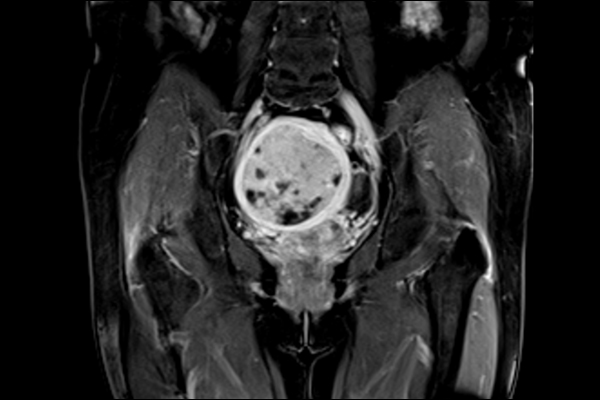

Chẩn đoán toàn thân: đầu, cổ, cột sống, khớp, bụng, tiểu khung, mạch máu

Tránh căng thẳng cho bệnh nhân nhạy cảm không gian, phụ nữ mang thai, ghế lưng lâu, khớp

Cho phép scan tư thế linh hoạt: nằm ngửa hoặc nghiêng, thuận tiện cho nhiều loại coil